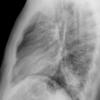

Case 2 Lingular pneum PA

Date: 04/17/2005

Views: 6028